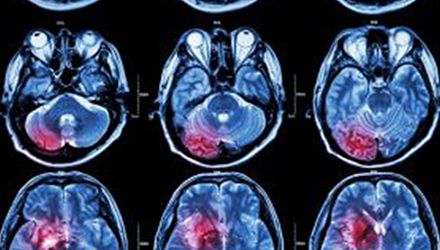

在這項研究中,研究人員使用功能核磁共振成像(fMRI)觀察大腦中血液含氧量的變化。研究人員首先研究了耳鳴患者和無耳鳴者的大腦活動,其目的是比較兩組受試者大腦處理情緒的方式。

在功能磁共振成像檢查中,受試者分別聽30種“愉悅”的聲音、30種“不愉快”的聲音和30種“中性”的聲音。這些聲音包括小孩咯咯笑,嬰兒啼哭,以及熱水壺?zé)_的聲音。

功能磁共振成像的結(jié)果顯示,當(dāng)暴露于情緒性聲音下,耳鳴患者大腦不同區(qū)域的活動比沒有耳鳴者的活動更強烈。接著,研究人員進(jìn)行了更深入的研究:耳鳴患者的大腦活躍性和耳鳴嚴(yán)重程度的關(guān)系。

調(diào)查結(jié)束后,再進(jìn)行功能核磁共振成像檢查。第二輪功能核磁共振成像顯示,那些耳鳴較輕的患者實際上使用了大腦不同的區(qū)域來處理情緒信息。

傳統(tǒng)觀點認(rèn)為,大腦中的扁桃體是處理情緒的關(guān)鍵,但此次研究發(fā)現(xiàn),那些不被耳鳴困擾的患者實際上使用更多大腦額葉來處理情緒。這類患者額葉活動更顯著的原因是,額葉通常更多地用于注意力、計劃和沖動的控制。